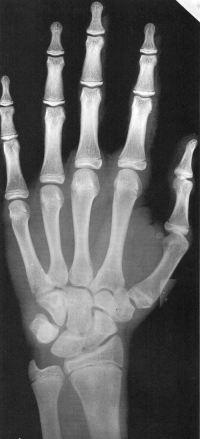

Sexo Masculino

10 anos